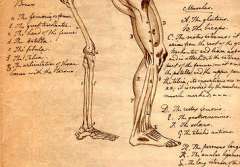

Bone Biology

Our Goal is to develop more sensitive in vitro and in vivo biological tests. The laboratory is currently developing a new animal model to evaluate osteolyitc potential of UHMWPE particles.